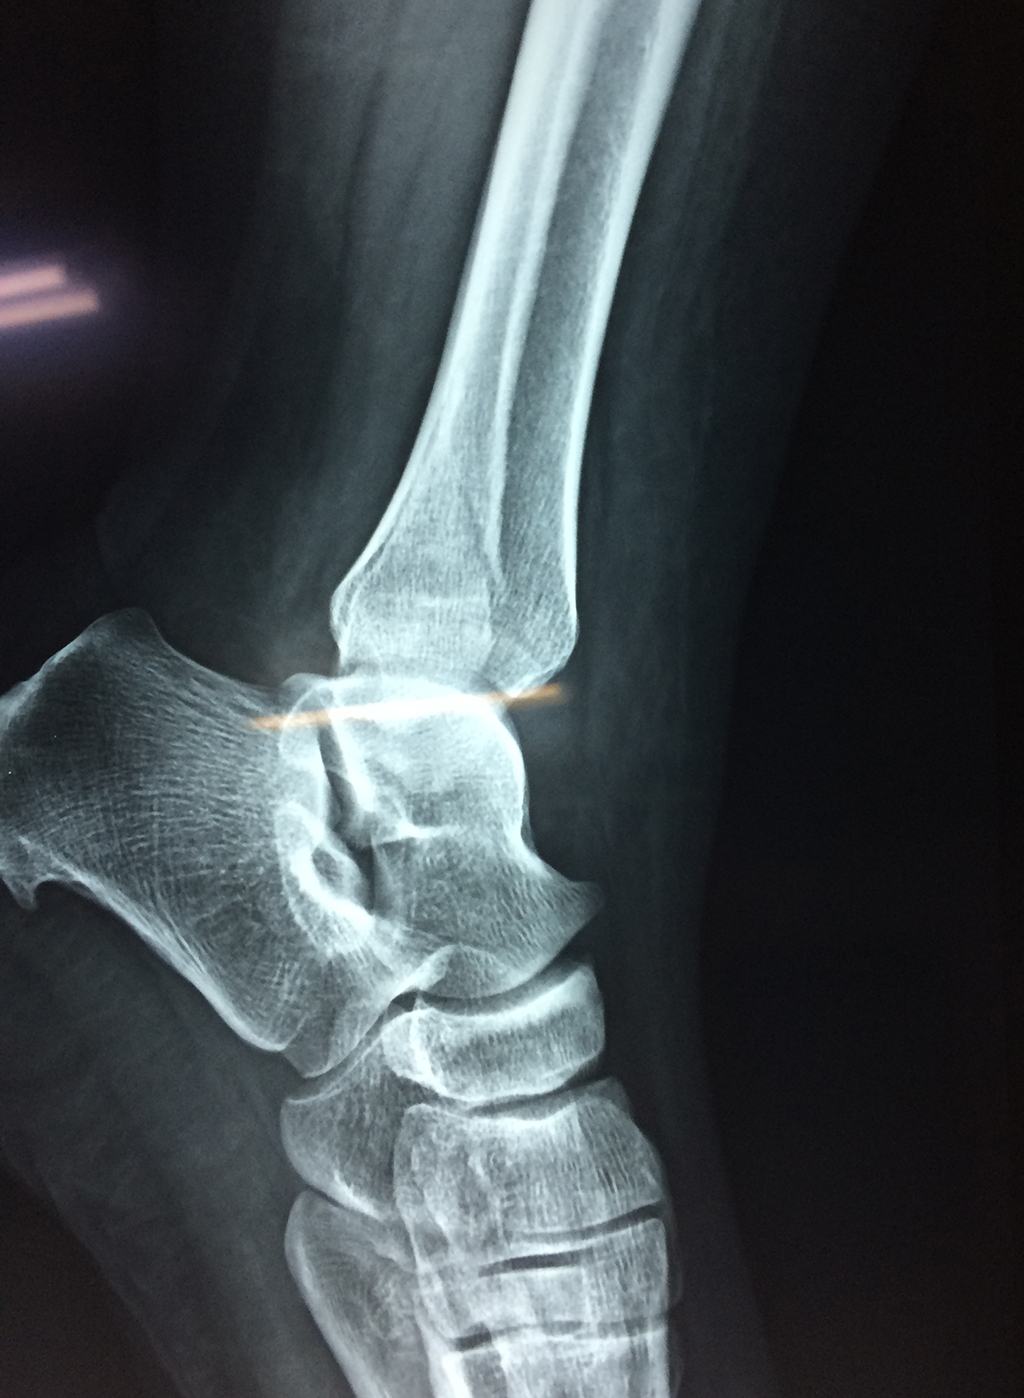

Algunas fracturas de tobillo pueden requerir cirugía si:

- Los extremos de los huesos están desalineados entre sí (desplazados).

- La fractura se extiende hasta la articulación del tobillo (fractura intra-articular).

- Los tendones o ligamentos (tejidos que sujetan los músculos y los huesos entre sí) están rotos.